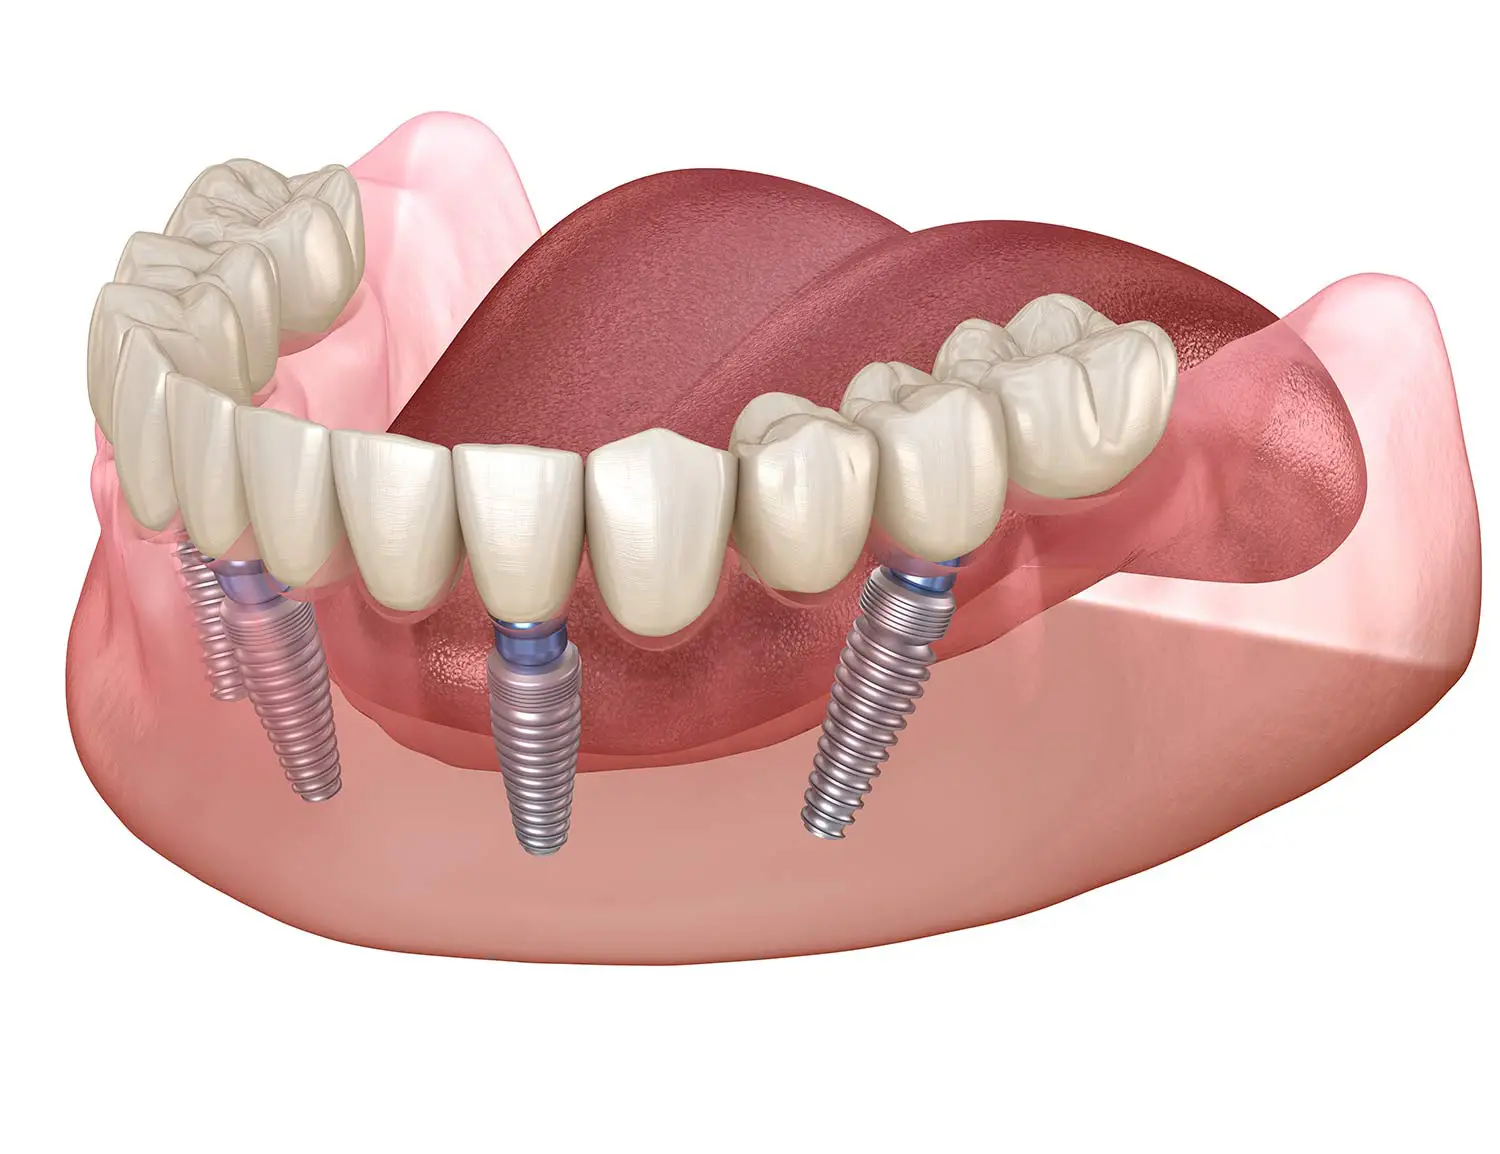

This technique strategically places four dental implants into the anterior (front) portion of the jaw, where bone density is typically more preserved.

By angling the posterior implants, they create a strong base for a full-arch prosthetic.

After the implants heal and integrate with your bone, a full set of lifelike teeth is securely attached. The result: a fixed, natural-looking smile that restores chewing and speech without slipping or adhesives.